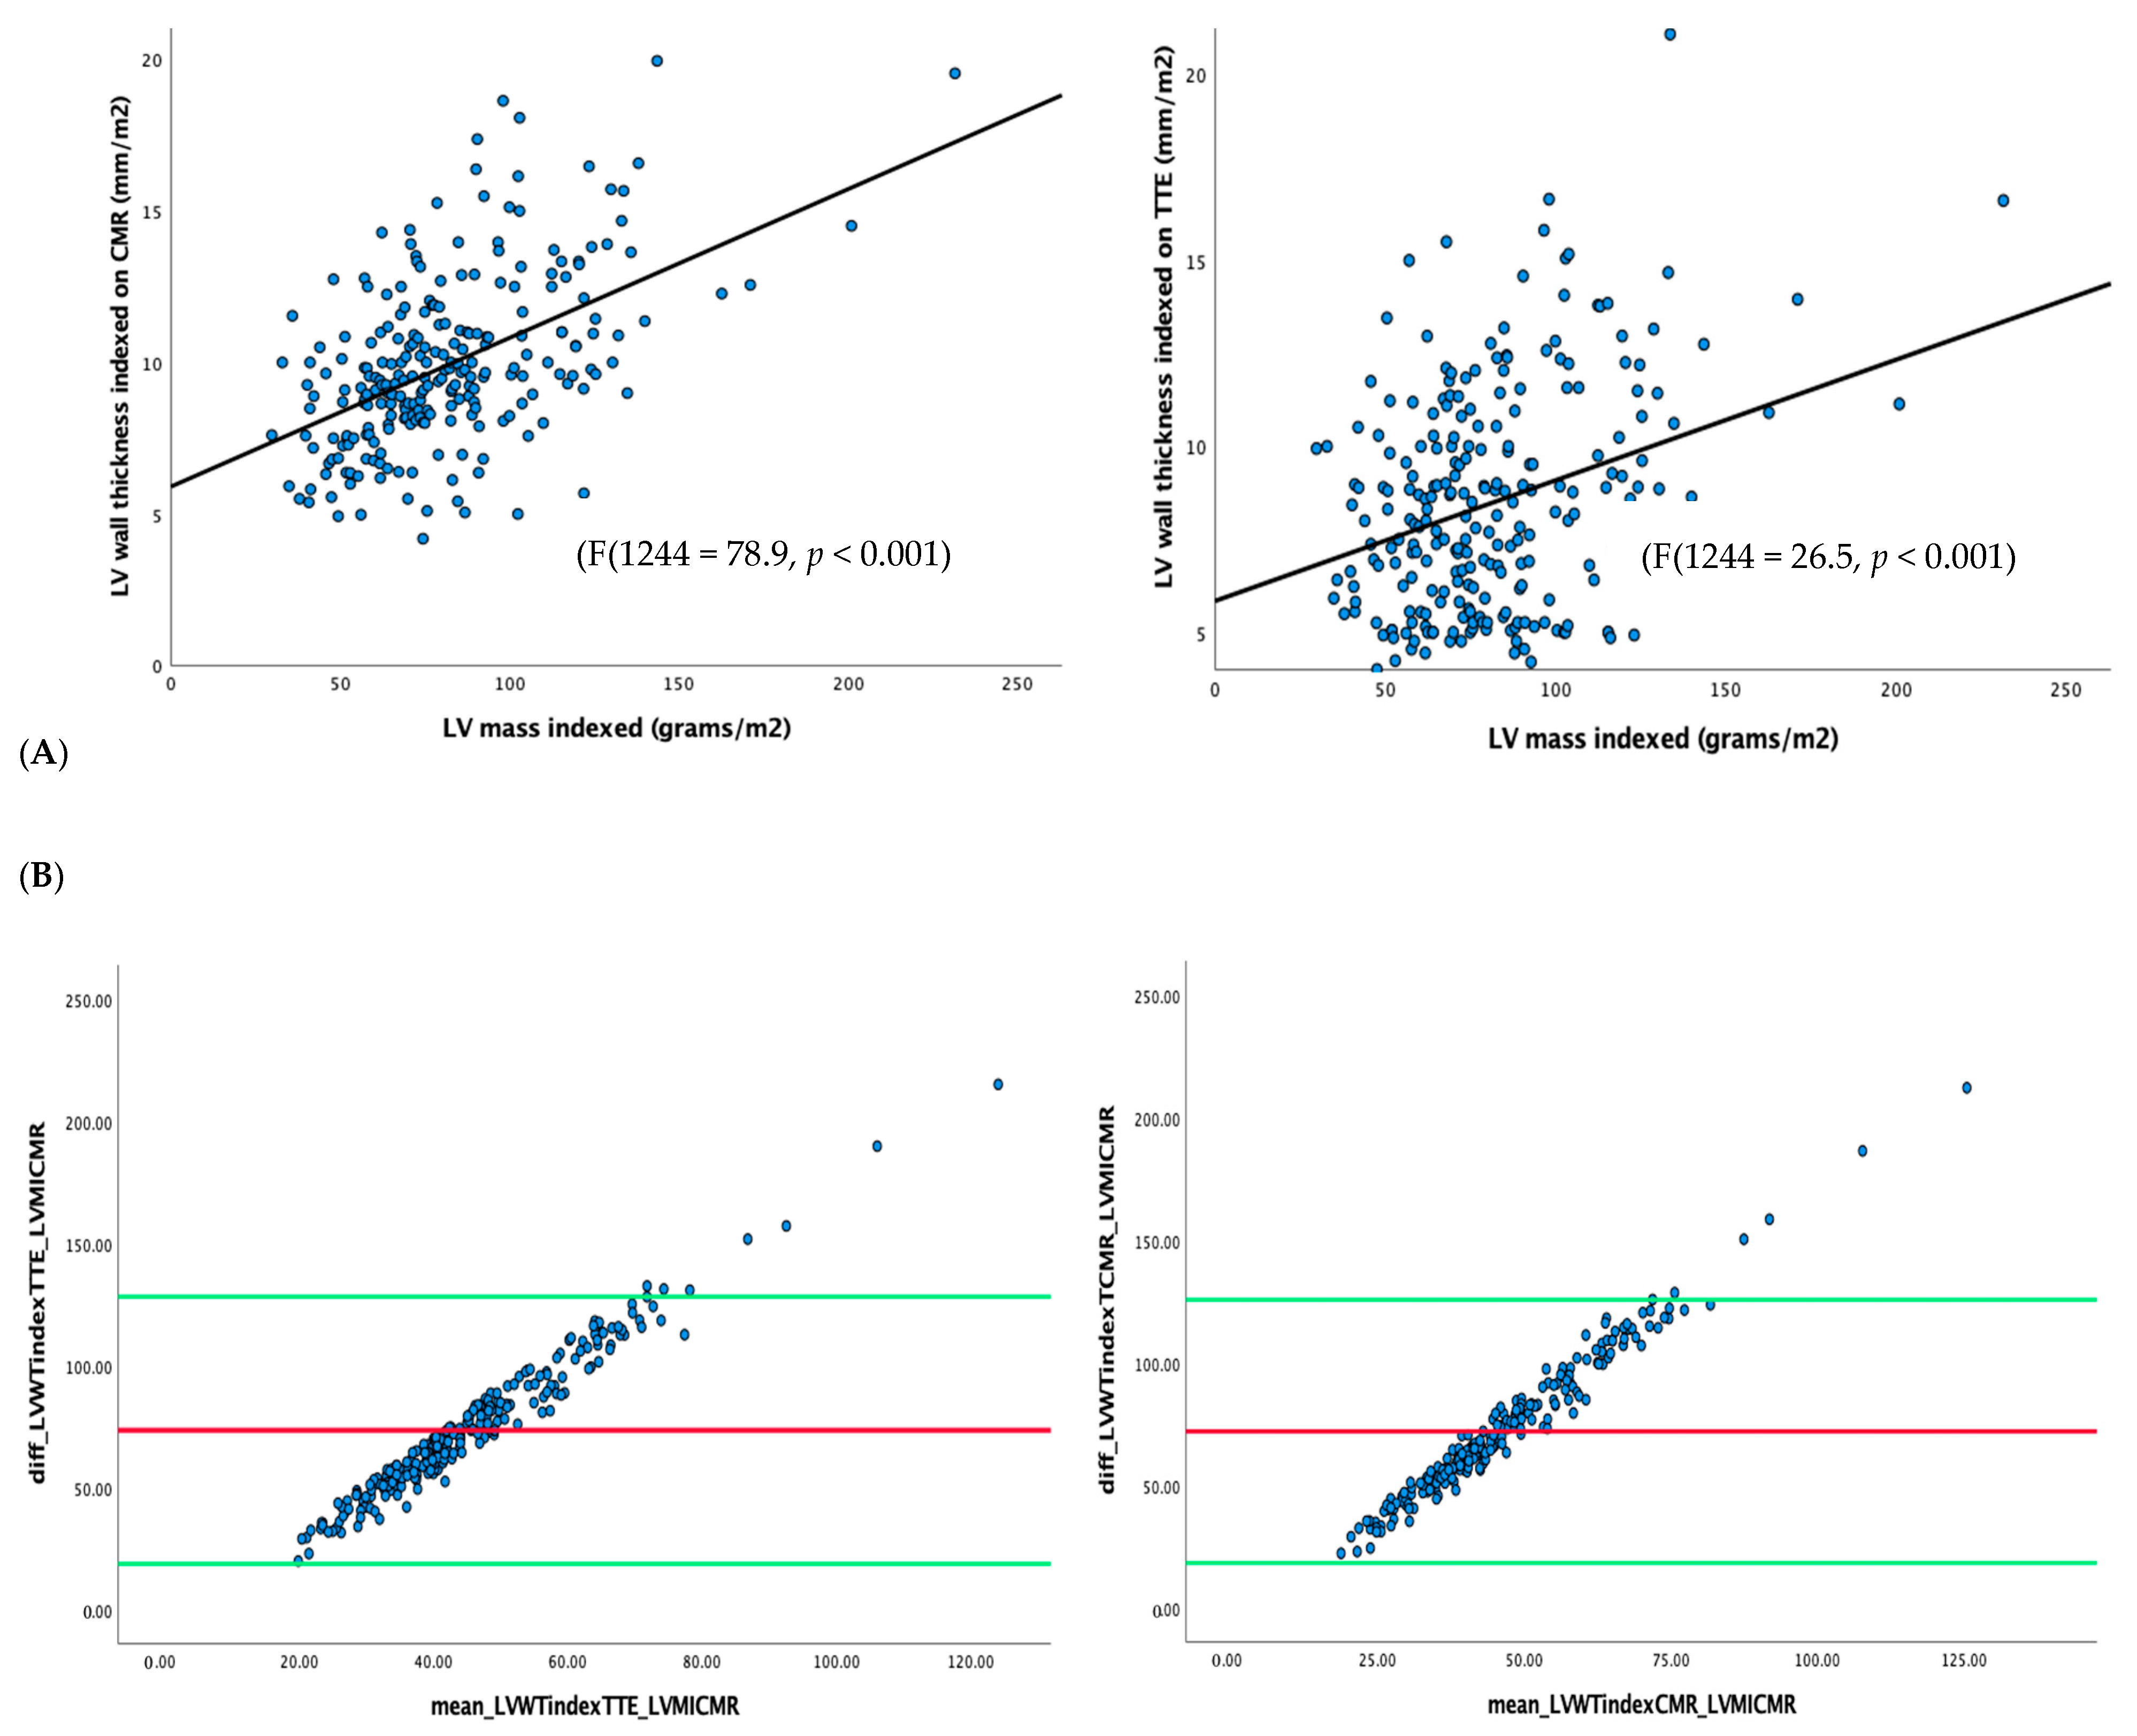

6.1. Correlation of LVWT and LVMI with LV Fibrosis

- LVWT using TTE or CMR was only weakly correlated with LVMI on CMR.